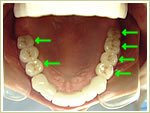

38歳 女性 インプラント埋入数:6本 画像拡大

治療前

治療前   治療前

治療後

治療後 治療後 治療後